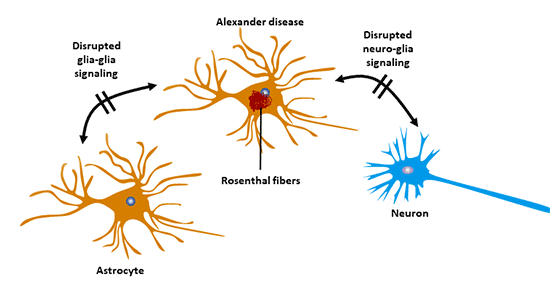

8.3 亞歷山大病(AxD)

亞歷山大病的發生與GFAP基因突變有關 [12]。這是由于GFAP基因突變導致GFAP裝配發生改變,GFAP聚集并在細胞內發生病理 性沉積。亞歷山大病屬于中樞神經系統退行性病變,它是一種遺傳疾病。

該疾病的特征是伴有漸進性肌無力嬰兒期發展, 并伴有進行性痙攣和精神障礙。

Messing等提出,通過靶向治療的方法可阻止 GFAP聚集及病理性沉積,提高蛋白酶體清除突變的GFAP的速度。

研究發現反義寡核苷酸抑制GFAP可以為治療亞歷 山大病提供一種治療策略[13]。

圖5 亞歷山大病與星形膠質細胞